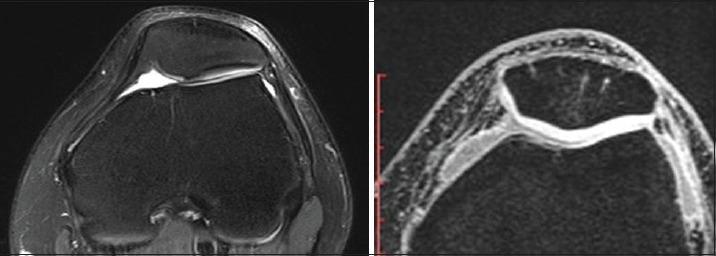

Patellofemoral osteoarthritis commonly occurs in older people, often resulting in anterior knee pain and severely reduced quality of life. The aim was to examine the effectiveness of arthroscopic patelloplasty and circumpatellar denervation for the treatment of patellofemoral osteoarthritis (PFOA).

A total of 156 PFOA patients (62 males, 94 females; ages 45-81 years, mean 66 years) treated in our department between September 2012 and March 2013 were involved in this study. Clinical manifestations included recurrent swelling and pain in the knee joint and aggravated pain upon ascending/descending stairs, squatting down, or standing up. PFOA was treated with arthroscopic patelloplasty and circumpatellar denervation. The therapeutic effects before and after surgery were statistically evaluated using Lysholm and Kujala scores. The therapeutic effects were graded by classification of the degree of cartilage defect.

A total of 149 cases were successfully followed up for 14.8 months, on average. The incisions healed well, and no complications occurred. After surgery, the average Lysholm score improved from 73.29 to 80.93, and the average Kujala score improved from 68.34 to 76.48. This procedure was highly effective for patients with cartilage defects I-III but not for patients with cartilage defect IV.

For PFOA patients, this procedure is effective for significantly relieving anterior knee pain, improving knee joint function and quality of life, and deferring arthritic progression.